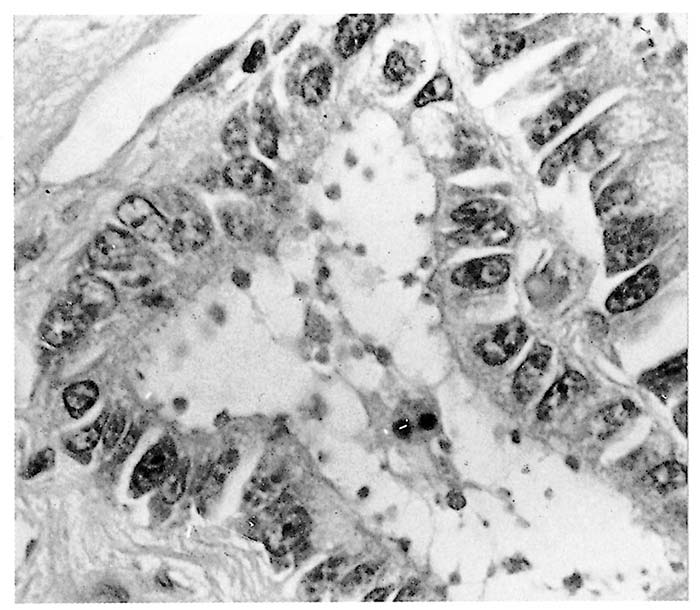

Stunting, fusion and cross-bridging of adjacent intestinal villi are seen histologically.4 In affected parts of the intestine, mucosal epithelial cells are often low columnar, cuboidal or even squamous and, in calves, there may be focal necrosis of epithelial cells in some areas.19, 23 The very small basophilic organisms, generally appearing as small dots, although ring or crescent-shaped forms may also be identified, are found embedded in the microvilli or just inside the distal cell membrane of epithelial cells (Figure 2) They are more easily demonstrated in tissue sections that are stained with Giemsa.5, 53 Extra-intestinal forms in the gall-bladder, mesenteric lymph nodes, trachea, lungs and uterus have been identified in immunocompromised humans49 as well as in pigs and sheep.20 In the bird parasite, C. baileyi, intestinal or respiratory infections are common.10

Following ingestion of oocysts by the host, sporozoites are released into the intestine where they penetrate the brush borders of the epithelial cells to develop into meronts. Although organisms appear to be attached superficially to cells, all stages are intracellular and are contained within a parasitophorous vacuole situated between the cytoplasm and outer cell membrane.19 The parasite is surrounded by the microvillous membrane, which fuses with the epithelial plasma membrane to form a thickened adhesion zone at the point of attachment to the host cell (Figure 1) There is also an adjacent comb-like structure formed by a folding of the parasite pellicle.43 These specialized structures are thought to facilitate the intake of nutrients by the parasite from the host cell. The meronts are 2 to 5 μm in diameter and contain eight merozoites that are released into the lumen of the gut. Second-generation meronts may occur, and these will contain four merozoites when mature. These merozoites invade new host cells where they undergo gamogony by forming macro- and microgamonts. The microgamont has sperm-like microgametes which, when released, fertilize the macrogamonts, which then develop into oocysts. Oocysts are round or ellipsoidal, and contain four sporozoites. It is generally accepted that sporocysts do not occur.32 Sporulation takes place within the host cell and is followed by the development of a resistant thick wall around some of the oocysts, which are shed in the faeces.19 Other oocysts, however, do not form a thick wall and the single unit membrane surrounding the sporozoites ruptures when these oocysts are released from the host cell. These forms are invasive and can infect epithelial cells and so reinitiate the development cycle, resulting in auto-infection mainly in immunocompromised hosts.17